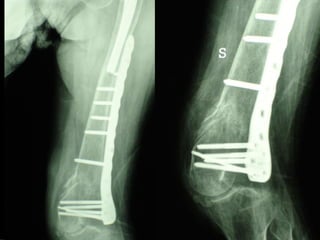

Dal Gennaio 2000 al Dicembre 2005 27 placche LISS di femore

INDICAZIONI COMUNI Fratture sovracondiloidee Fratture intercondiliodee Fratture diafisarie distali PARTICOLARI Fratture con grave osteoporosi Fratture periprotesiche

VANTAGGI CHIRURGIA MININVASIVA Mini Open Inserimento della placca sottocutaneo per scivolamento Viti percutanee Preservazione dei tessuti molli Ridotto danno vascolare Rapida ripresa funzionale

F, 68 y

LISS  NCB

NCB